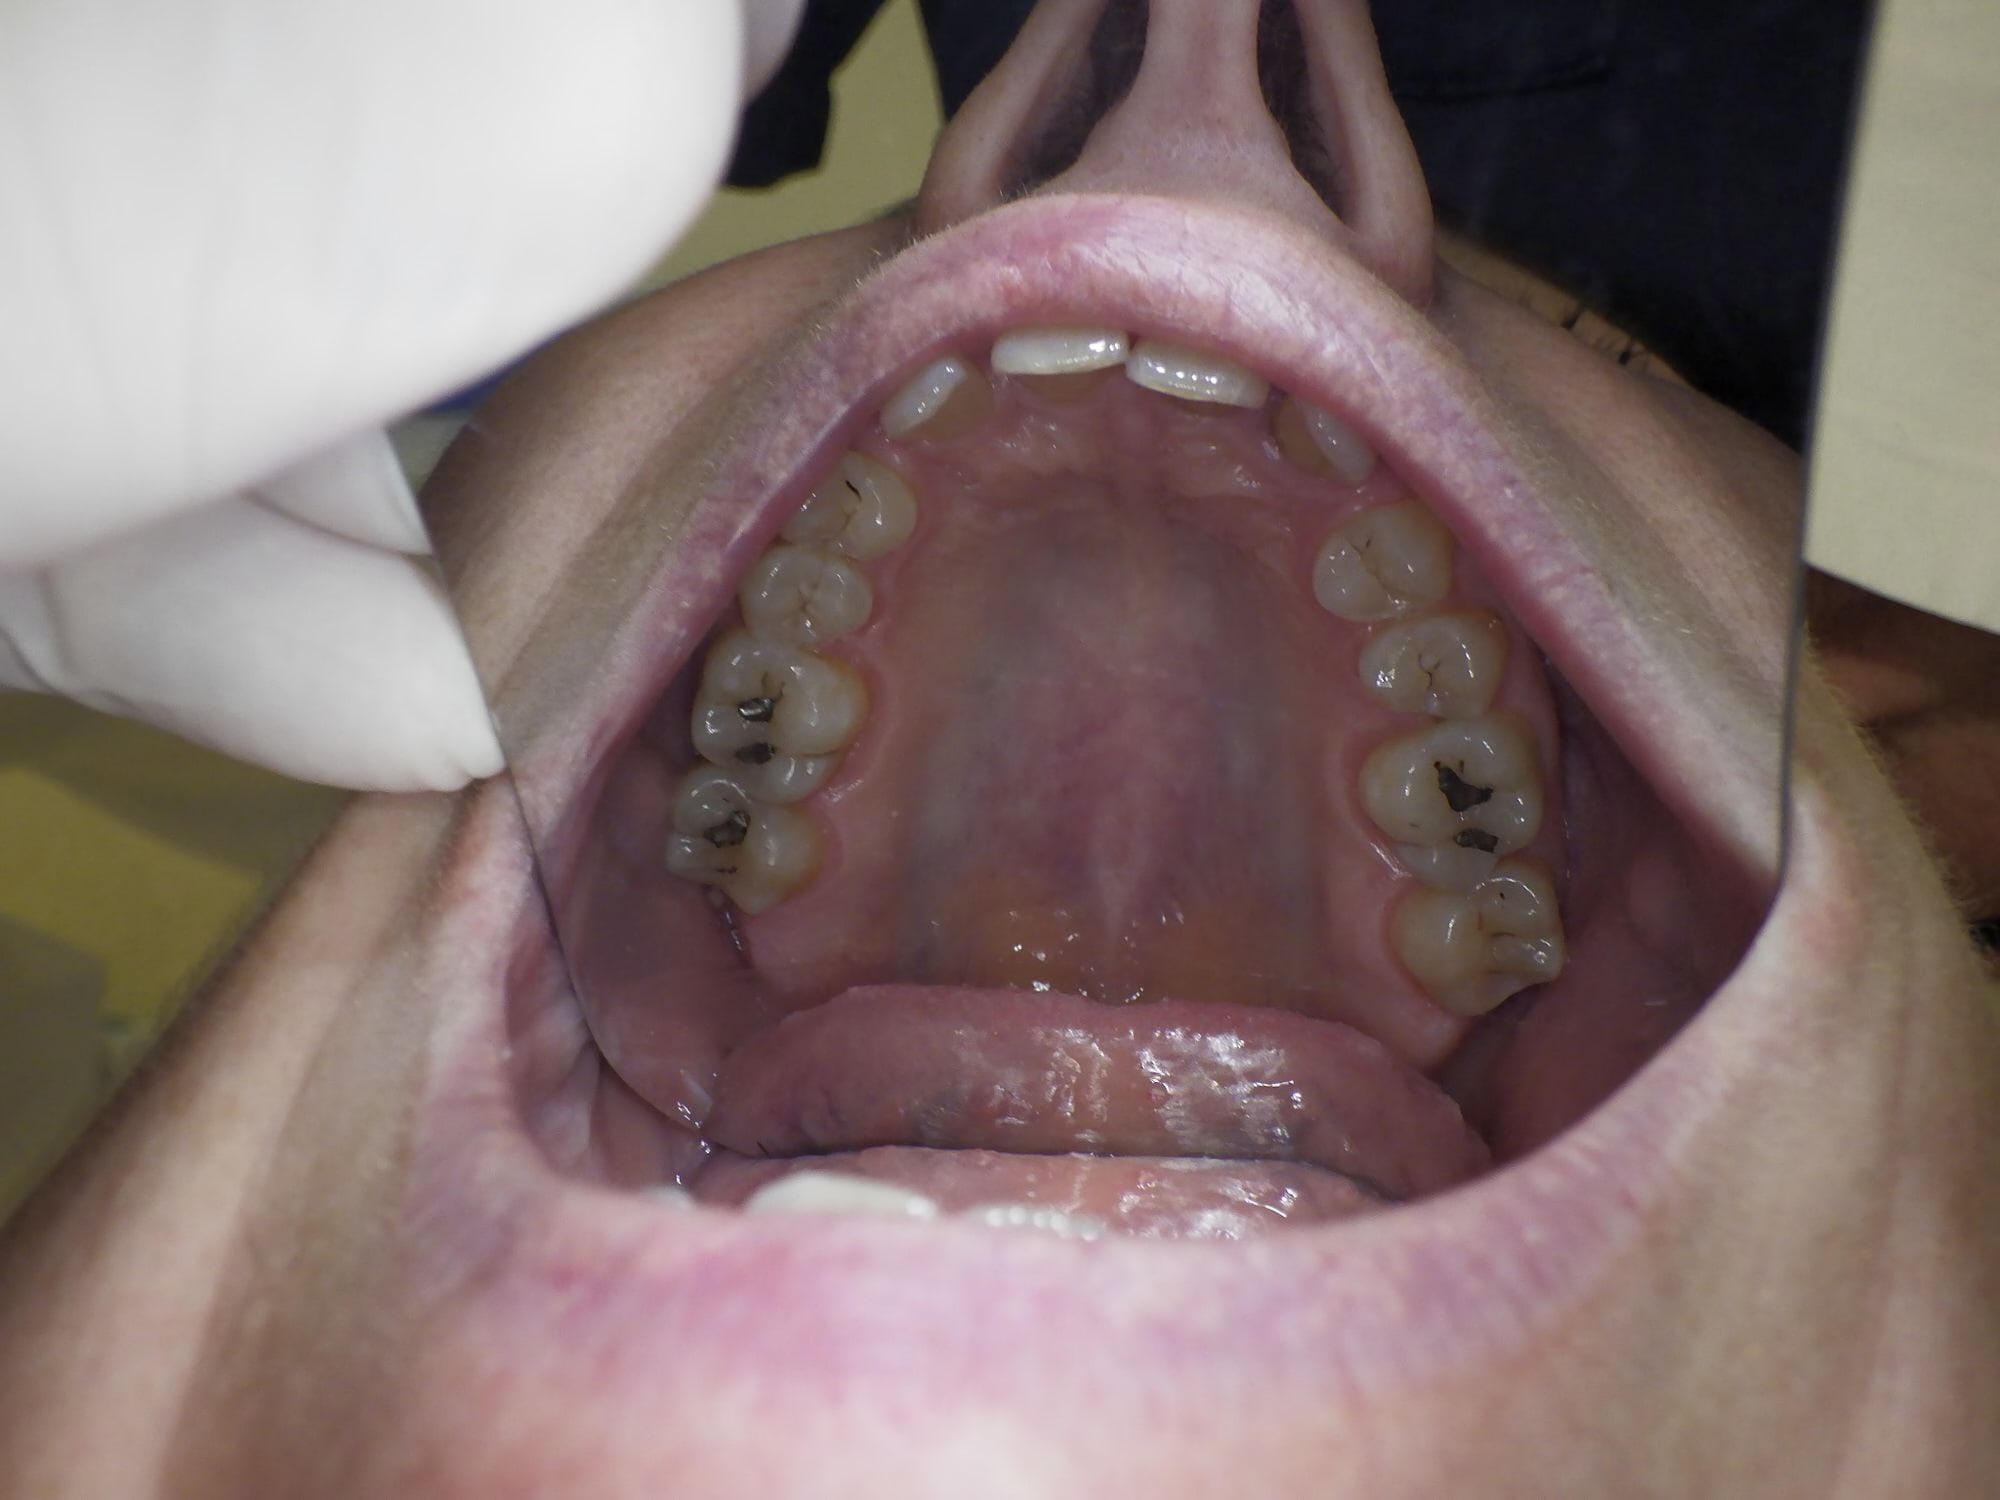

Bon afin de calmer le débat voici les photos de la patiente.

La 45 est en lingual et il y a eu de l'orthodontie suite à l'extraction de ses canines incluses lorsqu'elle avait 25 ans. (soit il y a 33 ans)

La 12 est en rotation mais ne bouge pas d'un poil.

Il y a un overbite énorme, donc pour l'équilibration, je ne vois pas trop comment faire.